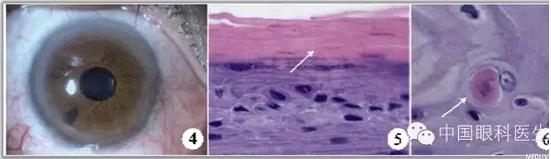

完善术前检査后,在爱尔卡因表面麻醉下,行右眼角膜上皮性肿物切除术,术中见上皮性肿物与角膜前弹力层无明显粘连,易分离,病灶基底光滑,给予彻底切除后,治疗性角膜接触镜覆盖创面,切除组织送病理,妥布霉素眼药水每日三次点眼,预防感染。一周后复诊去除接触镜,角膜创面生长良好(图4)。视力:右眼0.8。角膜病灶病理检査:右眼角膜上皮细胞增生、增厚,表面有角化物覆盖,部分区域上皮细胞增生活跃,呈异型性,基底膜完整(图5,6)。最后诊断:右眼角膜上皮不典型增生。半年后随诊未见复发。

图4角膜病灶切除术后,角膜透明,无云翳形成,视力1.0

图5右眼角膜上皮细胞增生,表面覆盖较厚的角化物(白箭)(HE×400)

图6右眼角膜上皮细胞增生活跃,呈异型性(白箭)(HE×1000)